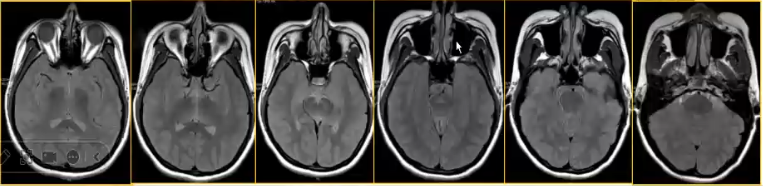

经蝶手术入路评价:切层平行于鼻蝶线,范围包括蝶窦和蝶鞍区